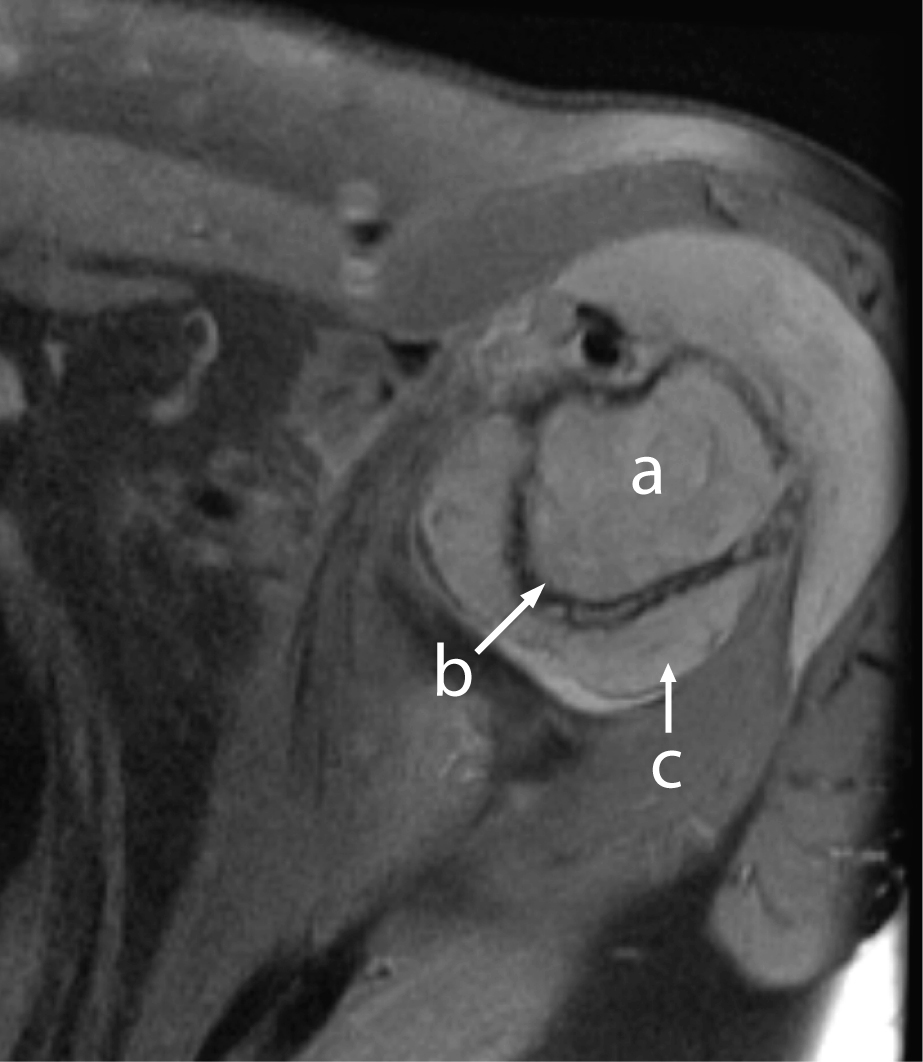

A 60-year-old previously healthy female presented with a 3-week history of increasing left shoulder pain; one week of nausea, abdominal pain, fevers, chills, and new-onset confusion. Laboratory evaluation demonstrated a white blood cell count of 22,600 per cubic millimeter with 28% blasts, hematocrit of 44%, platelet count of 102,000 per cubic millimeter, and calcium of 15.2 mg/dL. AML subtype M4 (according to the French-American-British classification) was confirmed by bone marrow biopsy. Cytogenetics showed trisomy 8 and t(5;13). Bone scan and bone survey were unremarkable. The patient was given standard induction therapy with cytarabine and idarubicin. Zolendronic acid was given for hypercalcemia. Left shoulder pain continued to worsen. Day 14 bone marrow biopsy showed persistent blasts; thus salvage therapy with mitroxantrone and etoposide was initiated. Shoulder pain improved partially, MRI of the left shoulder was performed showing a soft tissue mass in the glenohumeral joint space with cortical erosion of the proximal humerus (Fig 1). Biopsy was consistent with granulocytic sarcoma related to AML with infiltration into the bone and joint space, accounting for findings of hypercalcemia. Pain improved with chemotherapy and local radiation. Hypercalcemia responded to bisphosphonates. The patient had a transient remission, but soon relapsed and died from sepsis.

![]() Click for large image | Figure 1. MRI of left shoulder showing abnormal marrow signal of the proximal humerus (a) with cortical erosion (b) and soft tissue mass (c) with joint effusion. |